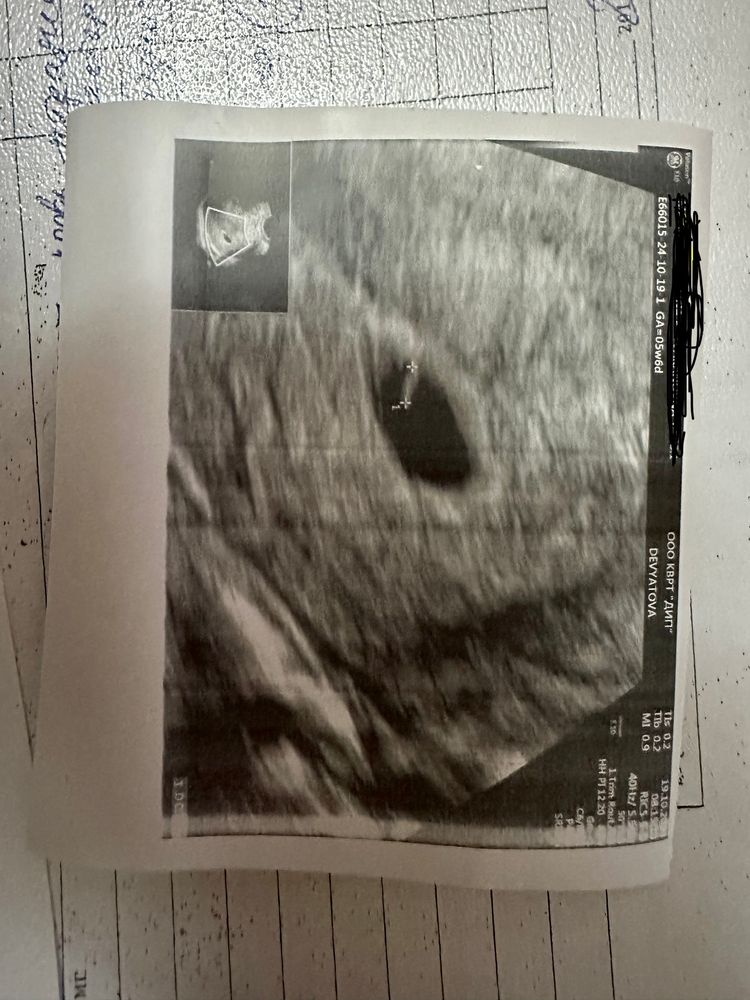

22дпп первое узи

Девочки , добрый вечер . После бхб , лечение , потом криоперенос 26.09 . Сегодня была намузи , сказали все нормально , но эмбриончик очень маленький . назначили контрольный узи на 30.10 ! Кто разбирается, все нормально или очень маленький ? 😕

У меня вообще на 23 дпп было только пя и жм, а на 30 сходила и все увидели)

Так что у Вас все отлично!

У меня на 21 ДПП не было эмбриона вообще, только ПЯ и желточный мешочек. У вас всё отлично.